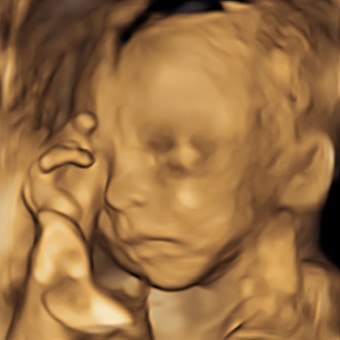

Welcome Miss Allison May 💕